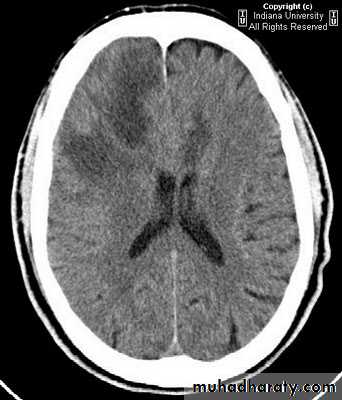

Metastatic Brain Tumours Pre contrast CT

Metastatic Brain Tumours Post contrast CT